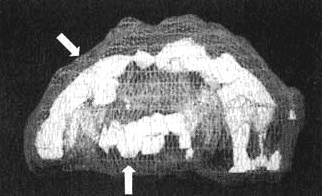

Глубокая лимбическая система

Иллюстрация к книге — Измените свой мозг - изменится и жизнь! [i_029.jpg]

Вид сбоку